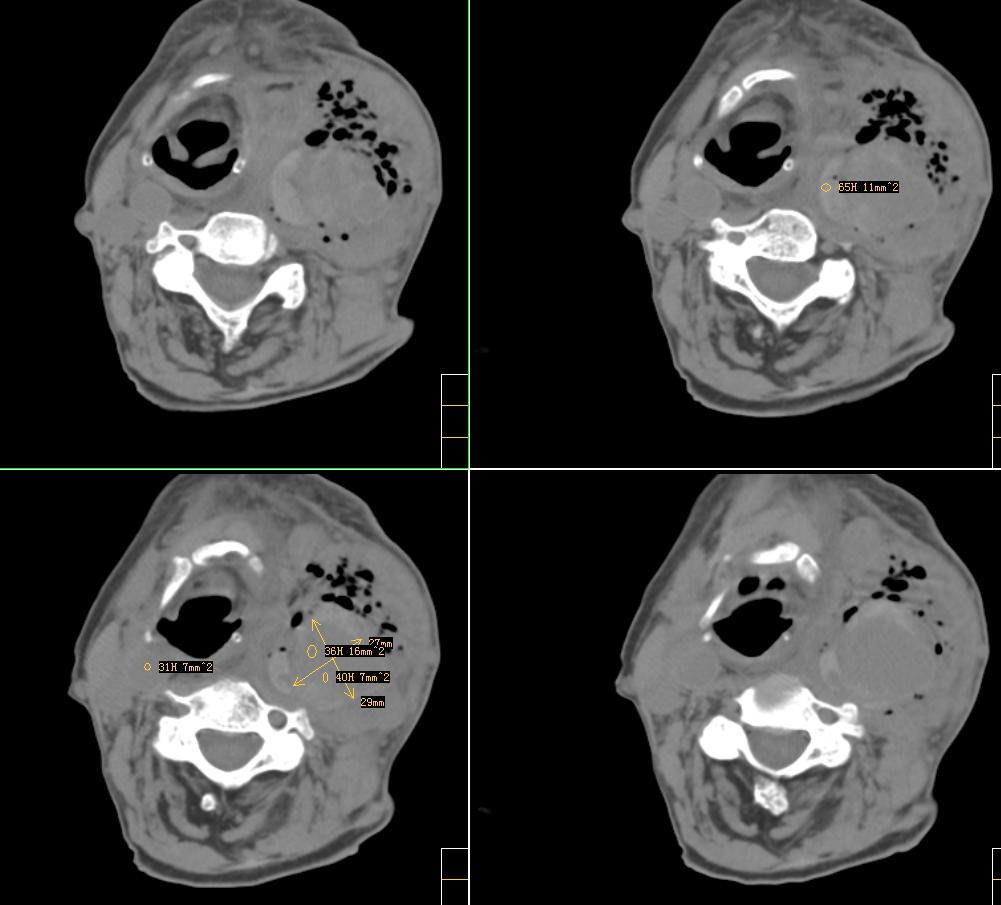

标题: CT4272:求助!颈部血管瘤破裂?

f、72y,左侧颈部发现包块及疼痛1周,彩超提示颈部血管破裂?

除上诉考虑外,那么多而且不规则、不定形的钙化还应该想到有颈部畸胎瘤的可能性。顺着思路继续,颈部畸胎瘤继发产气菌感染,并在颈总动脉局部形成小脓肿且浸蚀到血管壁。

左颈部血管增粗,周围软组织肿胀模糊,内有蜂窝状积气影,左侧甲状腺增大,气管受压右移,气管软骨环未受侵。结合病史较短考虑:左颈部脓肿破裂并血管瘤形成,左甲状腺瘤。

很遗憾,因患者高龄,高血压,肺心病、心衰,身体虚弱,未能进一步做增强扫描,临床上穿刺为动脉血,考虑颈动脉血管破裂(我觉得气体影不好解释),家属放弃治疗出院。[emb10]

考虑左侧甲状腺癌破坏气管,并颈部积气、淋巴结肿大。